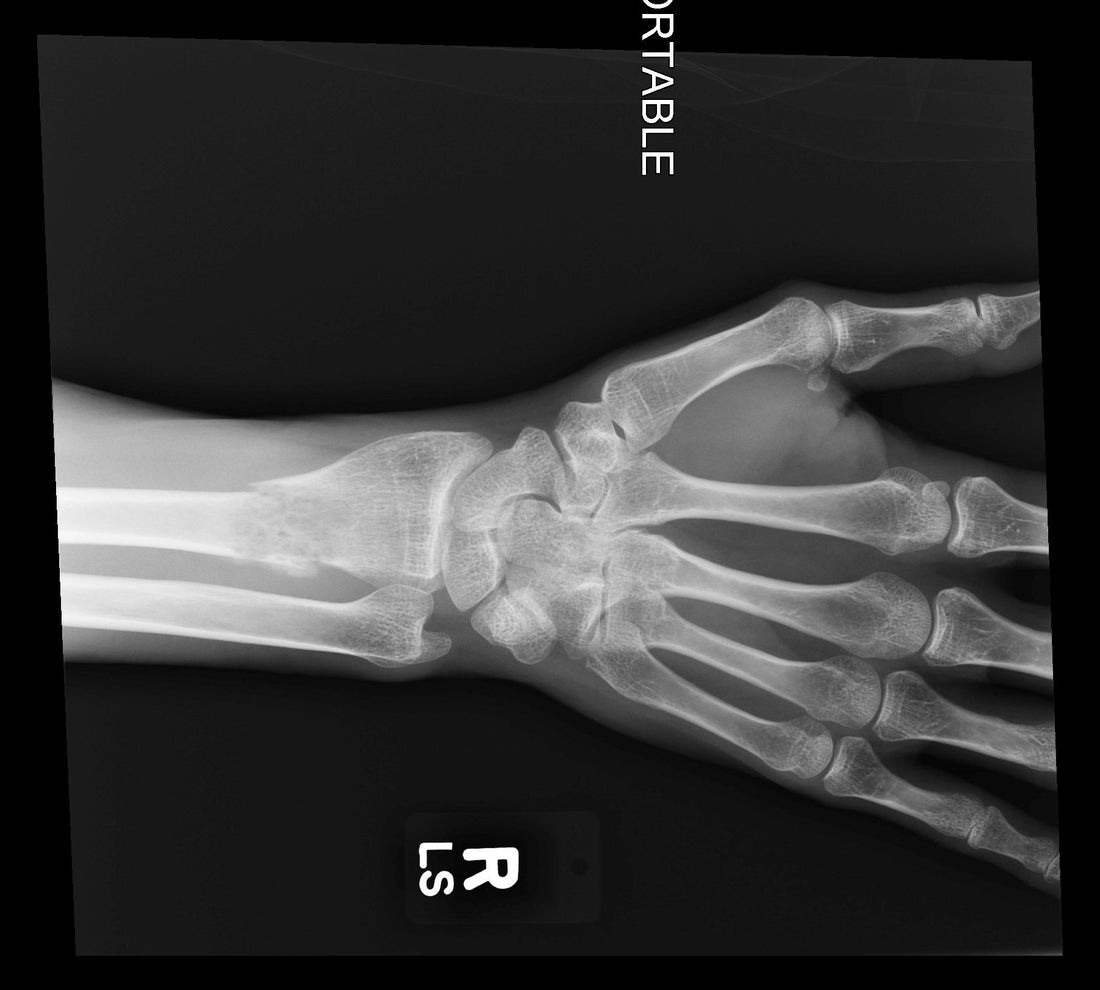

I also started feeling pretty ill. This was the infection. So I went to my nearest ER and got antibiotics. I told them, “Hey, as long as I’m here, why don’t you take a picture of my wrist, because I’m pretty sure it’s sprained.” And the X-ray revealed that my arm was broken, not sprained. The doctor said it looked like a pathological, metastatic break. I knew right away what it was.